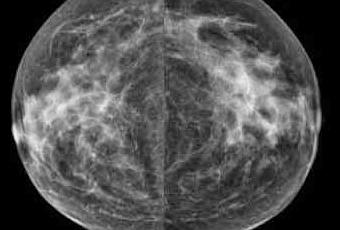

She finally came out and said I was free to go and apologized for the wait, but that my scans had looked so different from last year they really wanted to take a close look. That freaked me out for a moment and I asked her what she meant. Apparently my dense breast tissue wasn't so dense anymore. I asked if she minded showing me, and she took me in to look at the scans, from last year and this year, side by side. The 'suspicious" areas were diminished, and some completely gone. Apparently one of the perqs to aging (and having a hysterectomy) is that your hormones are no longer playing such great havoc. By next year they might look even less dense. So there was a "Yippee!!!" feeling, after all.